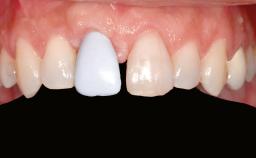

Shell Technique for Horizontal and Vertical Maxillary Bone Augmentation in a Partially Edentulous Patient with Aggressive Periodontal Disease

Prosthesis Type FDP

SAC Level Advanced

Defining Characteristics Up to three missing teeth to be replaced with an implant-borne restoration or restorations